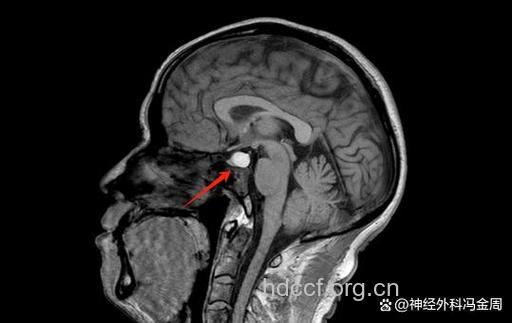

(二)磁共振检查

正常的垂体组织消失,代之以软组织肿块,约2×3cm大小,鞍隔隆起,视交叉受压,鞍底下陷,一侧海绵窦受侵犯。